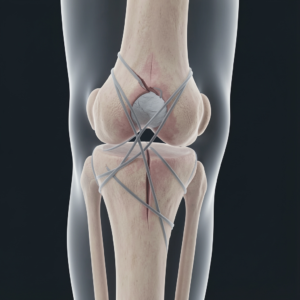

Uszkodzenia więzadeł kolana (ACL, MCL)

Zerwałeś więzadła w kolanie? ACL czy MCL – czym się różnią i co dalej?

Kontuzja więzadeł stawu kolanowego to jeden z najczęstszych urazów u osób aktywnych. Dwie najbardziej narażone struktury to ACL

Endoproteza stawu

Endoproteza to nie koniec, a nowy początek. Jak przygotować się do operacji i przejść przez rehabilitację?

Decyzja o wszczepieniu sztucznego stawu to dopiero połowa sukcesu. Druga połowa zależy od Ciebie – od Twojego zaangażowania w rehabilitację. Czy wiesz,

Choroba zwyrodnieniowa stawów (artroza)

Artroza, czyli gdy w stawie brakuje „oleju”. Czy można zatrzymać chorobę zwyrodnieniową?

Twoje stawy pracują jak precyzyjne maszyny – przez lata amortyzują wstrząsy i zapewniają płynność ruchu. Z wiekiem, ale też pod wpływem przeciążeń,